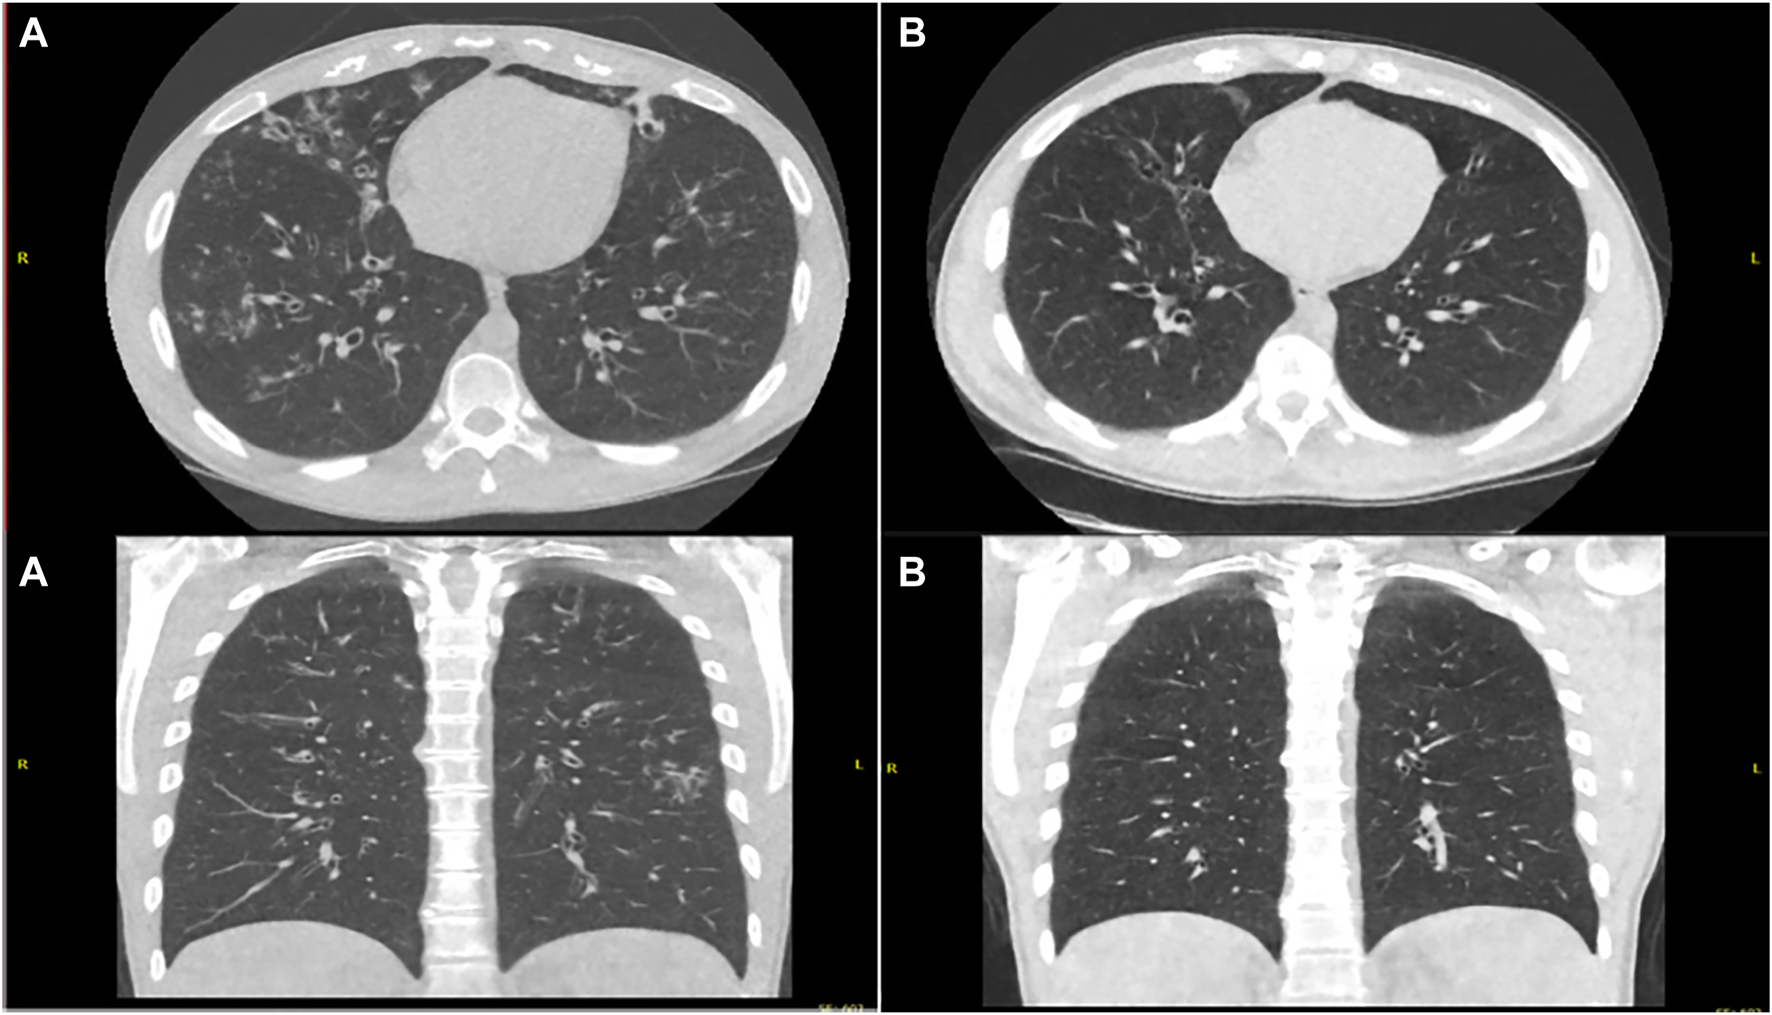

FIGURE 3

Ultra-Low Dose CT Thorax pretreatment (A) and post modified dose regimen (B) showing reduced burden of bronchiectasis, reduced caliber of bronchiectatic airways, decreased bronchial wall thickening and resolution of tree in bud opacification changes.